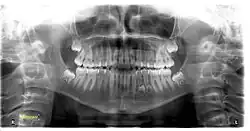

A set of human teeth under an orthopantomogram